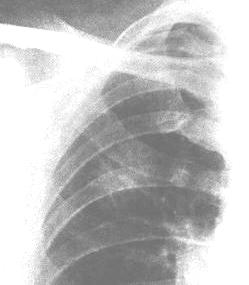

癌性疼痛X線圖1.腫瘤直接引起的疼痛